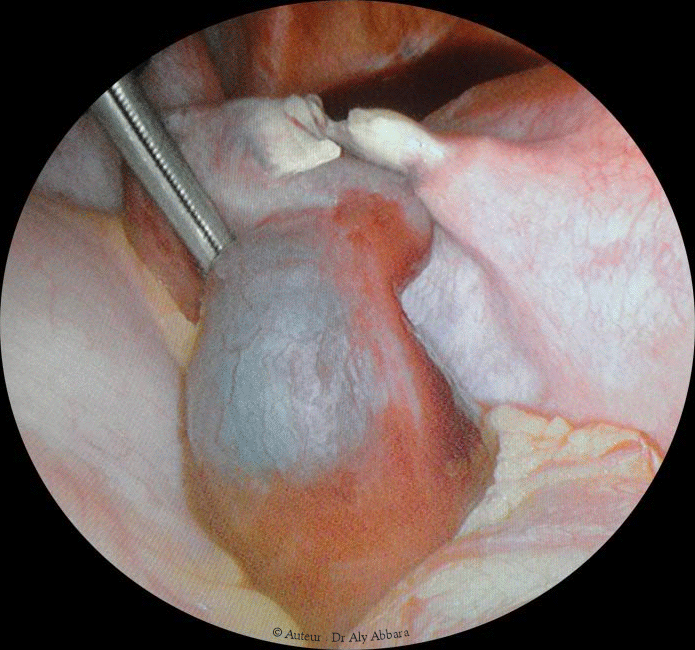

Grossesse ectopique tubaire post-stérilisation tubaire per-coelioscopie

• Images cœlioscopiques mettant en évidence une grossesse extra-utérine tubaire gauche chez une patiente bénéficiant 14 jours auparavant d'une stérilisation chirurgicale par coagulation-section tubaire bilatérale per-coelioscopique.

Cette grossesse extra-utérine tubaire était compliquée par une hémopéritoine pelvien étendu jusqu'à la région péri hépatique (espace de Morison ou espace interhépato-rénal).